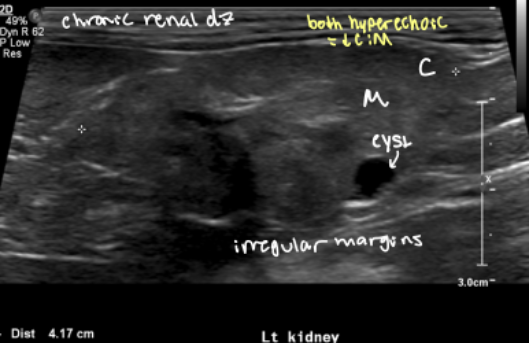

End-stage renal disease – kidneys also small and irregular

Renal dysplasia – kidneys also small and irregular

2 reasons for decreased CM junction distinction

chronic renal disease

renal dysplasia